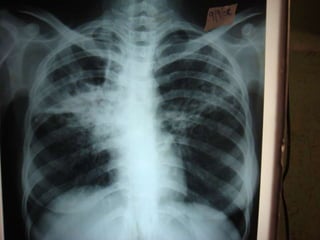

cxr

TRC Opinion(30/9/08): 	          Sputum AFB repeat neg; Sputum C/s for TB taken. Even though pt is sputum AFB negative with symptoms of  TB with  increasing infiltrates in CXR advice to con ATT-CatII Even after all these treatment measures pt continued with fever but breathlessness,Cough and expectoration subsided.pt advised to continue cat-II ATT until c&sreport arrives.